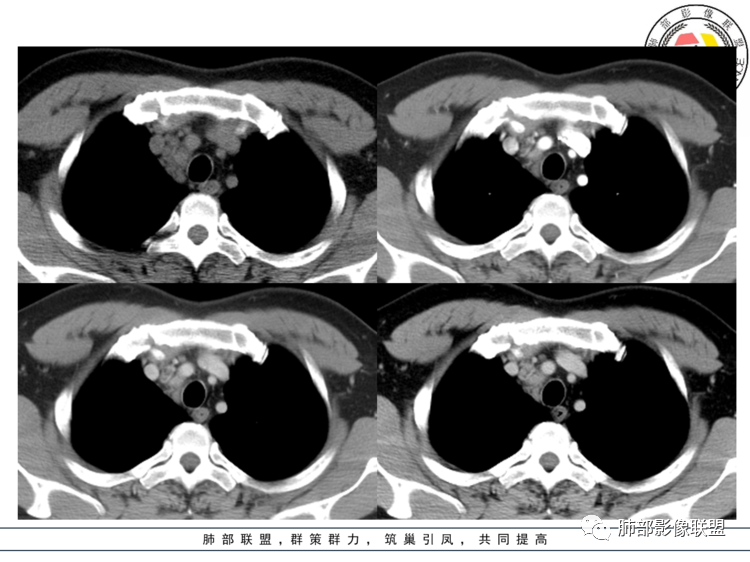

南边 :

定位没问题吧

中纵隔

上腔静脉后方,偏外;定位需要鉴别的是胸膜来源SFT

这些层面上腔静脉明显外推,不支持胸膜来源

这里有的结构:神经、淋巴结、脂肪

1、神经来源:鞘瘤、付节瘤

2、淋巴结:CD(透明细胞)、淋巴瘤、转移瘤

3、脂肪:脂肪肉瘤

4、异位:甲状腺腺瘤、胸腺瘤

强化过于明显:付节瘤、CD、异位甲状腺腺瘤

动脉期显著强化,结节呈“门状结构”附近多发子灶——CD!

至于周围、内部血管影我认为血供丰富的肿瘤都有